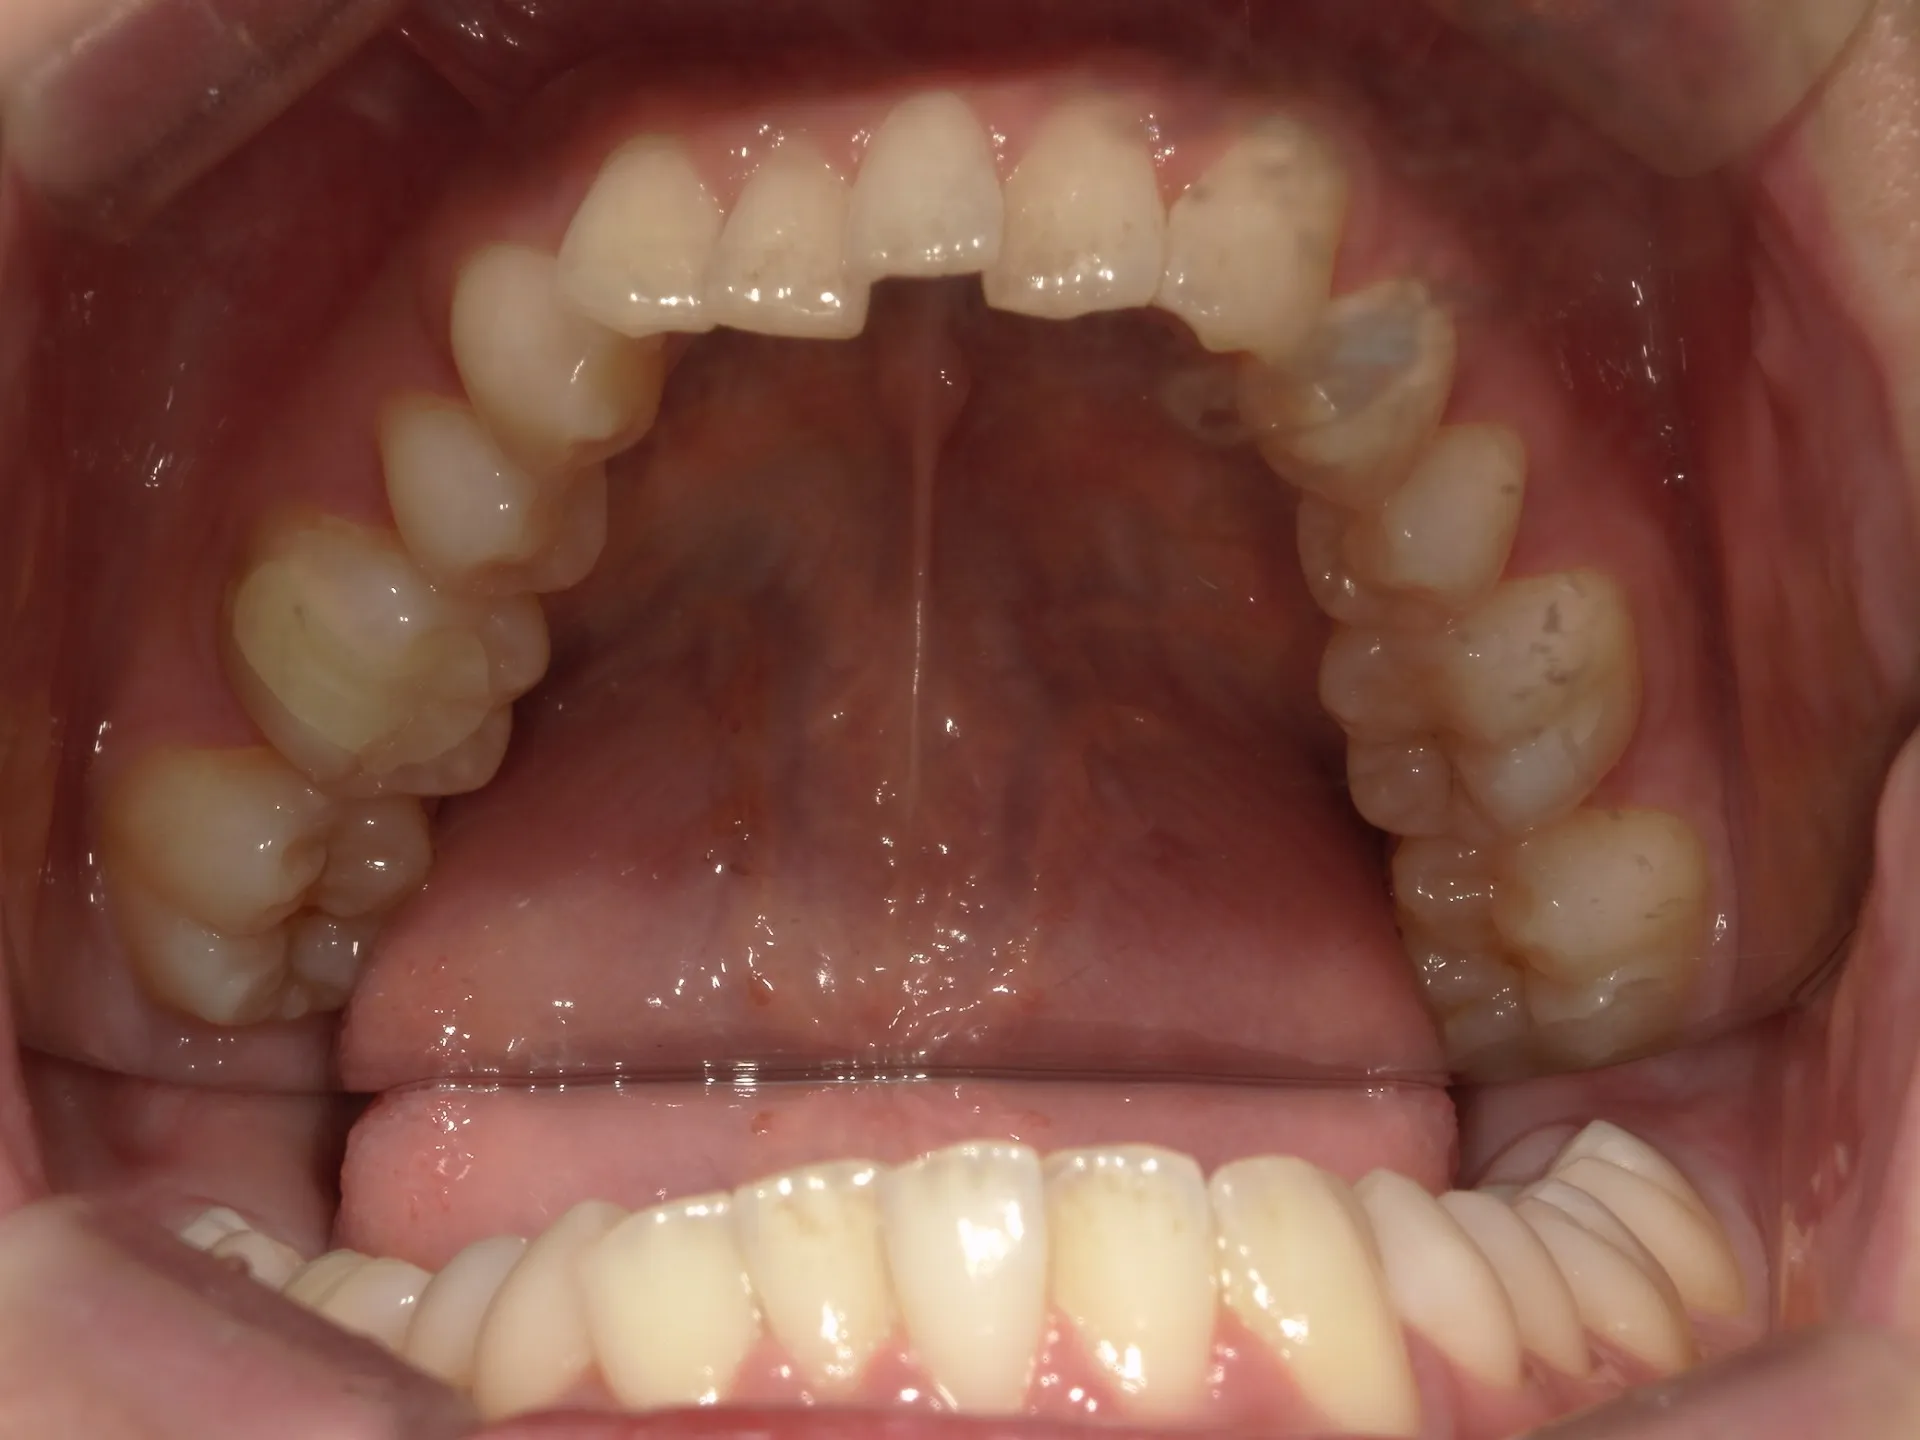

大きく飛び出してしまった前歯の矯正と変色の治療を希望された症例をご紹介いたします。